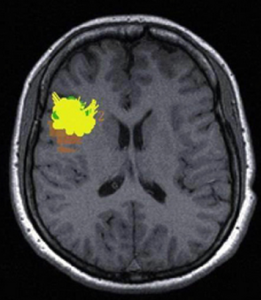

交通性腦積水可由多種原因引起,而各種原因所造成的腦脊液通路受阻部位不盡相同,CT和MRI有時可幫助明確病因。腦基底池的阻塞可由炎症和腫瘤引起,顱底感染和炎性肉芽增生在增強CT上可出現強化現象,在MRIT2加權圖像上有時也可出現高信號灶。在葡萄狀囊尾蚴病人,可出現基底池的大囊腫樣改變。

假如腦脊液可以經過基底池到達大腦半球凸面,那么病變可能是位於蛛網膜顆粒,蛛網膜顆粒位於上矢狀竇中線兩旁,正常情況下被吸收的腦脊液通過上矢狀竇入靜脈竇。蛛網膜顆粒病變的最常見原因是蛛網膜下腔出血,可由外傷、動脈瘤破裂或AVM出血所致,這種病人由於出血刺激和紅細胞的機械作用,使蛛網膜顆粒受損,在CT和MRI上表現為急性腦積水,腦室系統短時間內明顯擴大。此外,化膿性腦膜炎也可引起急性腦積水;腫瘤的腦膜轉移則表現為隱匿性腦積水過程,在成人以顱外惡性腫瘤(如乳腺癌)轉移多見,兒童則以顱內腫瘤播散為常見(如髓母細胞瘤的蛛網膜下腔播散);白血病或淋巴瘤侵犯腦膜亦可導致交通性腦積水。